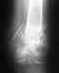

Оптимальным для подобных переломов является закрытое штифтование с блокированием. Не очень понятно, почему стали лечить именно аппаратом.

По одной проекции в аппарате выглядит неплохо, но неизвестно, как расположены фрагменты на профильной проекции.

Чтобы предположить, как долго быть в аппарате, надо смотреть снимки не только в двух проекциях, но и в динамике. Те. сразу после наложения аппарата, через месяц, через два...